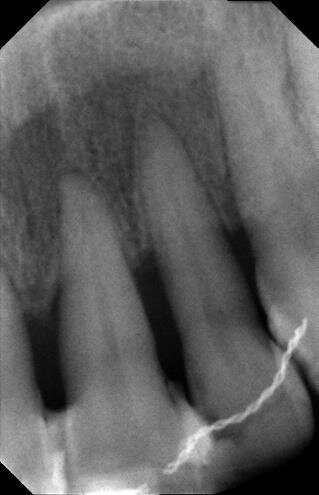

La paziente (che agirà in giudizio) 55 anni, fumatrice con scarso controllo dell’igiene domiciliare, in cura nel 1998 per parodontopatia cronica e compromissione dei quattro incisivi superiori (Figg. 1-5) per dodici anni, viene trattata con terapie chirurgiche e non2. Nel luglio 2010, dopo ben 12 anni di mantenimento di tali denti, si presenta all’osservazione dell’odontoiatra per la rottura dello splintaggio, riferendo di aver subito un accidentale trauma facciale.

Tutto ciò viene dettagliatamente spiegato sia verbalmente, sia descritto nel “Consenso informato” che la paziente sottoscrive dopo aver richiesto un secondo consulto presso un altro studio. Il trattamento estrusivo dei due incisivi laterali inizia nel gennaio 2011 (Figg. 7, 8). Al raggiungimento del risultato desiderato (Figg. 9, 10), si attendono 60 giorni di “stabilizzazione” dell’osso alveolare18 (Figg. 11, 12).

La fase chirurgica viene pianificata con la preparazione iniziale (igiene orale, controllo emato-chimico delle condizioni della paziente, prescrizione della profilassi/terapia antibiotica19-20 e della sospensione del fumo). Il 23 giugno 2011, vengono estratti i due incisivi laterali (Figg. 13, 14) e inseriti contestualmente due impianti Xive (Dentsply) di diametro 3,8 mm e lunghezza 15 mm (Figg. 15, 16), dimensioni ottimali per la successiva protesi (ponte di 4 elementi da 1.2 a 2.2 con 1.1 e 2.1, elementi “intermedi”).